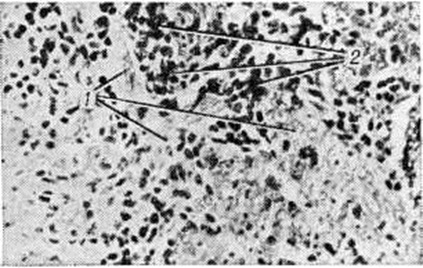

Макроскопически Лимфоэпителиома имеет форму узла или крупнобугристого образования плотноэластической консистенции покрытого первоначально неизменённой слизистой оболочкой, бледно-серого цвета на разрезе. Микроскопически Лимфоэпителиома построена из крупных пластинчатых клеток, лежащих разрозненно или образующих компактные гнезда и рыхло связанные тяжи (рисунок, 1). Опухолевые клетки имеют различную форму, контуры их неотчётливы; цитоплазма бледная, иногда отростчатая; ядра крупные, светлые, обычно округлой или овальной формы, с фуксинофильными ядрышками. В ткани Лимфоэпителиома иногда встречаются очаги плоскоклеточной дифференциации вплоть до ороговения отдельных клеток и образования так называемый раковых жемчужин. Строма опухоли состоит из нежно-волокнистой соединительной ткани, инфильтрированной лимфоидными клетками (рисунок, 2) и пронизанной многочисленными капиллярами. Выделяют так называемый тип Шминке, характеризующийся ретикулярным расположением эпителиальных и обилием лимфоидных клеток, и тип Рего с компактным размещением эпителиальных клеток и небольшим количеством лимфоцитов в виде отдельных очагов.

Микроскопическая картина лимфоэпителиомы: 1 — гнезда и тяжи опухолевых клеток, 2 — скопления лимфоидных клеток в строме.